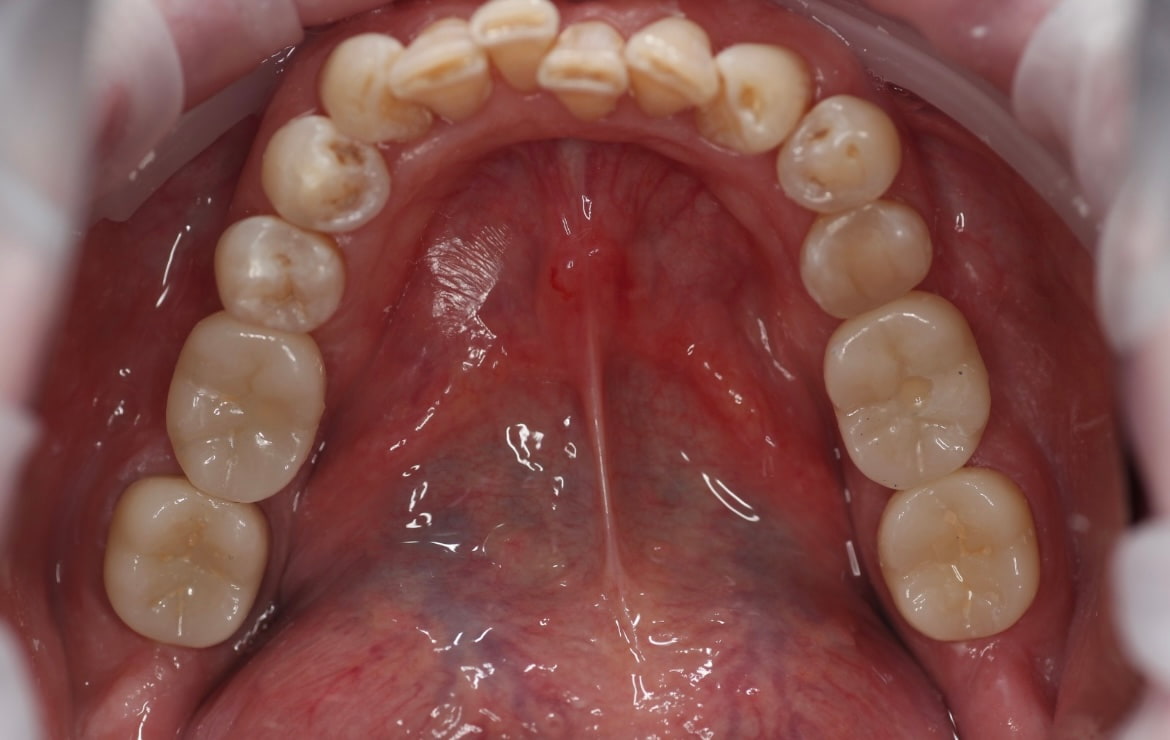

Обточка зубов 12-23 под дц коронки, ретракция 000 и 00 нитями, снятие рабочих оттисков а-силиконом, изготовление временных акриловых коронок прямым методом через силиконовый ключ, фиксация на TempBond.

Готовая работа зафиксирована на сиц Fuji I через 7 дней.